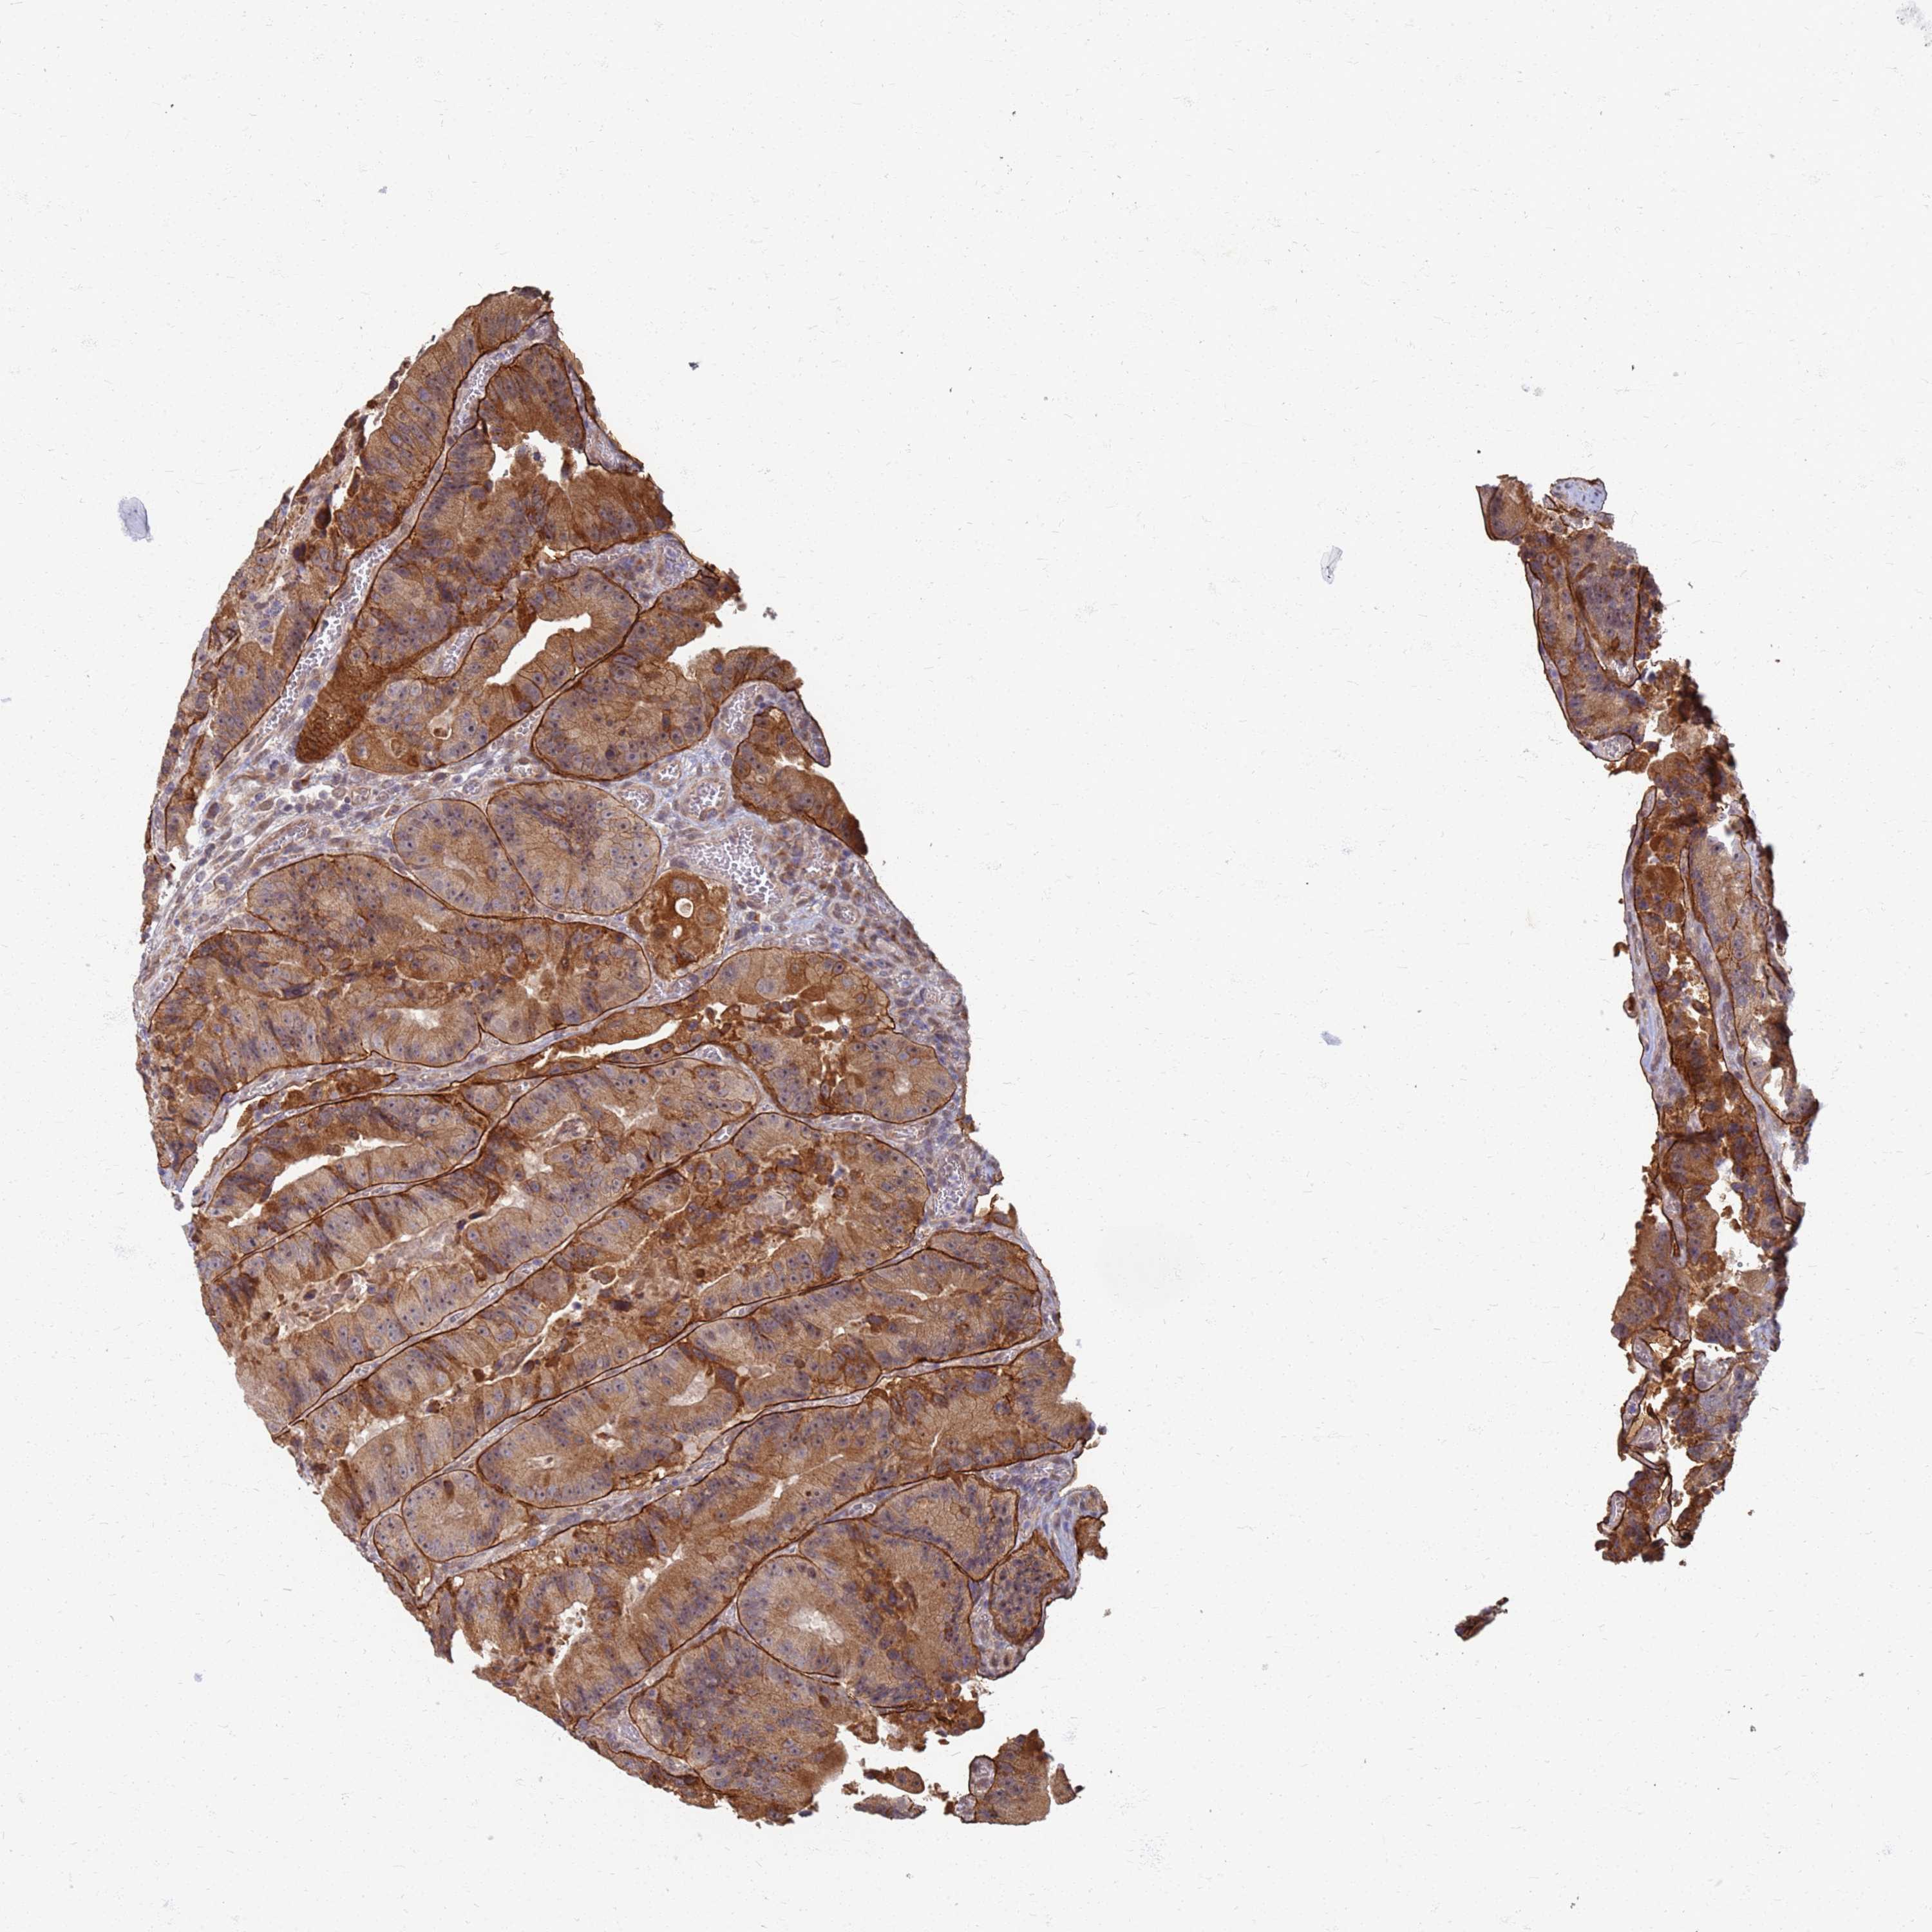

CANCER COLORECTAL CANCER Show tissue menu

ANTIBODIES

AND

VALIDATION

Colorectal cancer

Human cancer

Colon adenocarcinoma